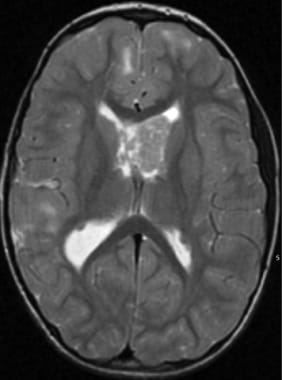

SEGAs require resection if they produce hydrocephalus or significant mass effect. If a gross total resection can be achieved, recurrence is unlikely. The authors have had good results with stereotactic placement of a modified angioplasty balloon catheter via a burr hole in proximity to the lesion. The balloon is then gradually inflated over several days to create a tract for removal of the SEGA. At final operation, the balloon is deflated, the catheter is removed, and the tumor is resected. [27] An illustrative example is shown in the following images.

Subependymal giant cell astrocytoma prior to stereotactic insertion of balloon catheter as seen on T2-weighted MRI.